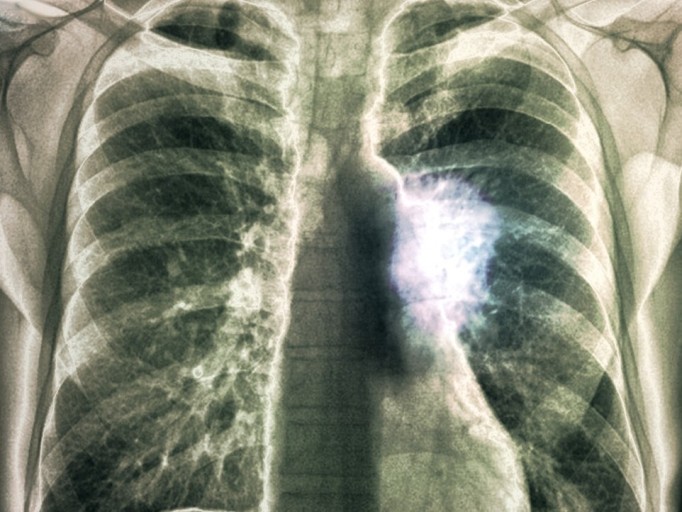

폐암 초기증상 7. 혈담

혈담도 있습니다. 혈담이란 기침 후 피가 나오거나 가래에 피가 섞여 나오는 것입니다. 선홍색의 비교적 선명한 피가 나오면 폐암을 체크해 보아야 합니다. 이것은 암세포 그리해서 폐가 괴사하기 출혈이 발생하여 그런 것입니다. 실제로 폐암 환자의 25%가 혈담을 하였다는 것을 보여주는 통계가 있습니다.